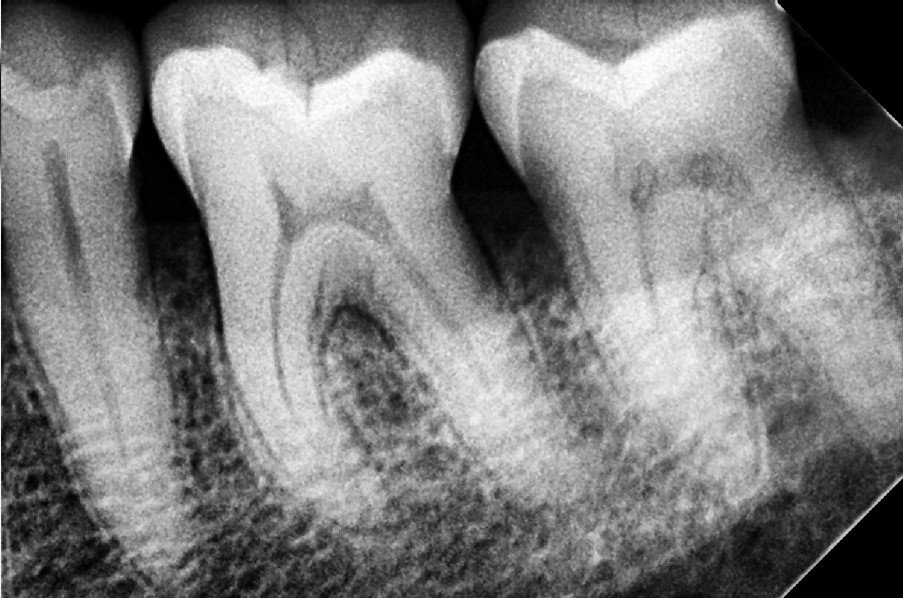

1. Comprehensive Consultation & Digital X-rays

We start with a thorough check-up using digital X-rays to assess the condition of the tooth and surrounding bone. This helps us plan the extraction precisely.